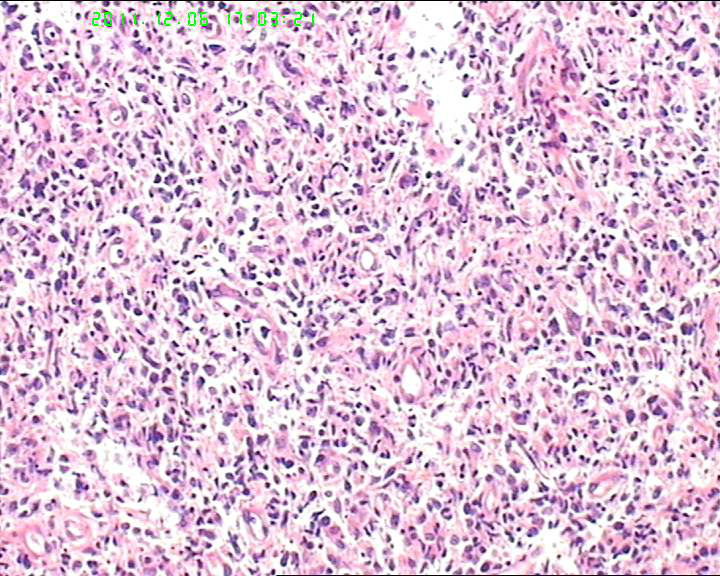

53岁女性患者,鼻腔肿物,中线恶网?韦格尔肉芽肿?

患者流脓涕1年,加重1月。左鼻腔息肉样增生物,质软,易出血。

送检灰白色绿豆大组织4块。

组织内见大量形态各异的异型明显的细胞,弥漫分布,背景见肿瘤素质,首先考虑结外NK/T细胞淋巴瘤,鼻型;恶黑待排。